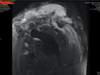

Pyomyositis with abcess in deltoid

Septic AC joint

DC osteomyelitis

GH joint preserved

CC instability or bad x-ray?